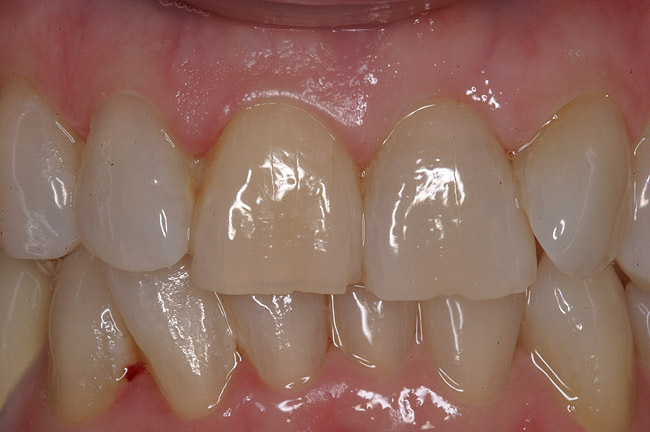

Figure 8  The post-implantation and post-restoration view shows esthetically pleasing, symmetric crowns and mucosal contours, with the Nos. 7 and 10 implant prostheses blending in imperceptibly with the natural dentition. Restoration courtesy of Dr. Jeffrey Warren.

Figure 8